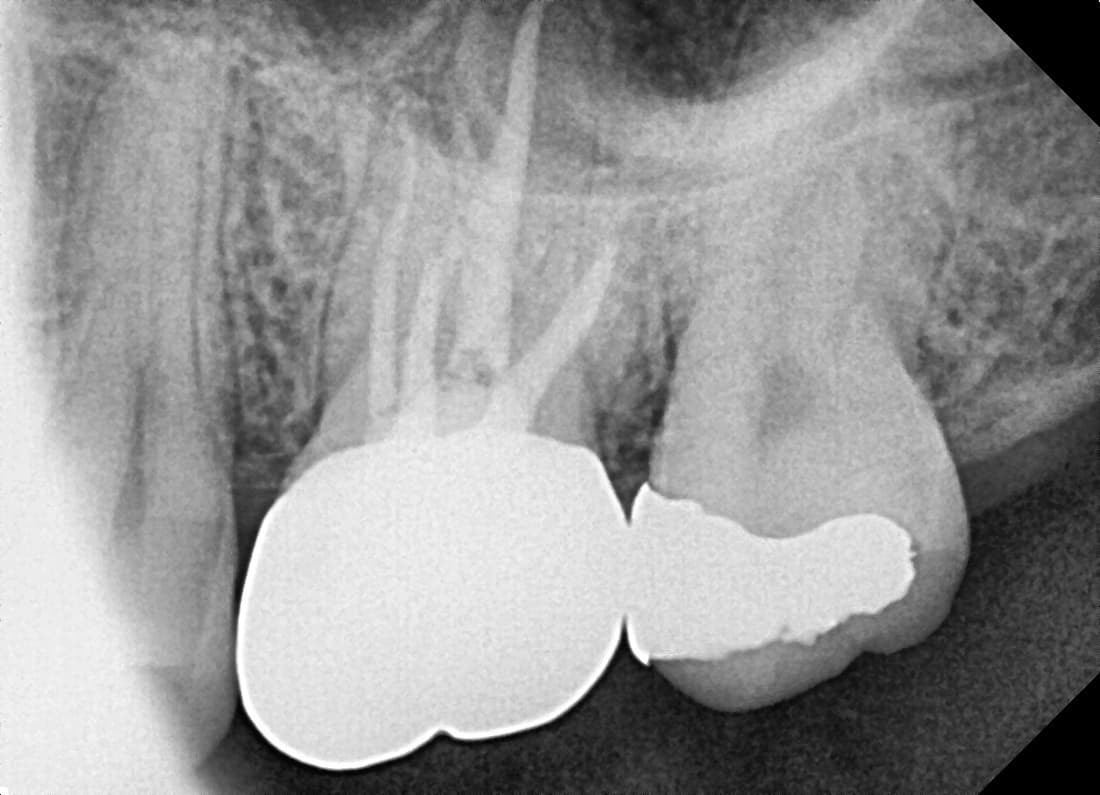

치근단절제술

뿌리 끝까지 염증이 번진 앞니

Before

After

재신경치료 및 치근단절제술 후 병소 완치